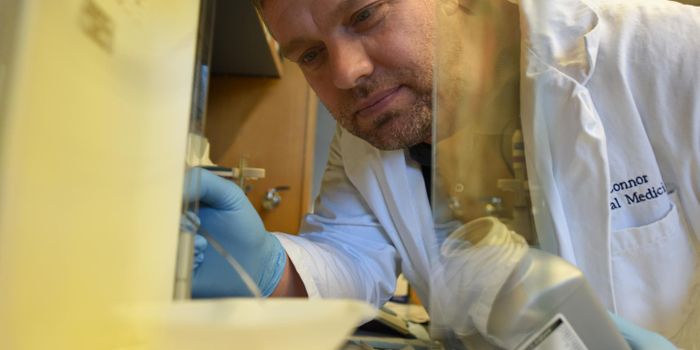

MAY 15, 2019Cell & Molecular BiologyIn doctors' first year of training as interns, they work very long hours in a demanding environments. It has a biologica ...